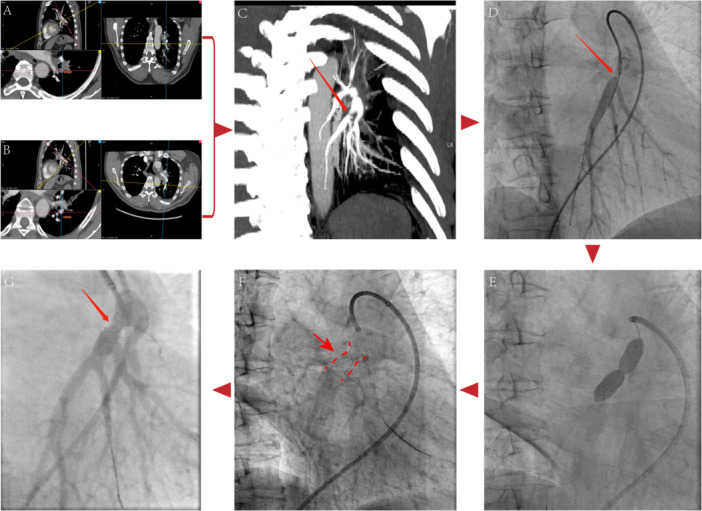

Fibrosing mediastinitis (FM) can block pulmonary vessels and airways, hindering treatment efficacy. Pulmonary artery (PA) stenting might provide a solution in such cases. This study involved 30 patients who had 49 PA stenting procedures for FM. Data on baseline characteristics, CT pulmonary angiography images, stent patency, and hemodynamics were collected. Patients with FM often had a history of chronic obstructive pulmonary disease (15/30), tuberculosis (12/30), and pneumoconiosis (11/30). Patients exhibited typical symptoms such as dyspnea, exercise intolerance, and cough. FM appeared as multiple bilateral shadows with enlarged hilar and mediastinal lymph nodes. Our study found that the PA involvement alone was predominantly in the left and right lower basilar trunk, with the left lower pulmonary arteries (LLPA) involved in 80% of cases and the right lower pulmonary arteries (RLPA) in 100%. Moreover, over 2/3 of patients showed involvement of both PA and pulmonary vein (PV), mainly in the bilateral upper lung lobes, then in the right middle lobe and left lingual lobe. After PA stent implantation, patients showed enhanced tricuspid annular plane systolic excursion (20.6 vs. 18.5, p < 0.001) and reduced right atrial diameter (35.5 vs. 37.3, p = 0.042), along with significant gains in 6-min walk distance (465.2 vs. 392.7, p = 0.002) and improved World Health Organization functional class (p < 0.001). Hemodynamic parameters improved after PA stent placement with significant reductions in systolic pulmonary artery pressure (PAP) (51.1 vs. 64.2, p < 0.001), mean PAP (28.4 vs. 35.2, p < 0.001), pulmonary vascular resistance (4.7 vs. 5.9, p = 0.004), and stent gradient (11.2 vs. 33.4, p < 0.001), along with increased patency (84.8% vs. 28%, p < 0.001), and fractional flow reserve (0.84 vs. 0.44, p < 0.001). Over a median follow-up of 331 days (range 45-980), no significant stent stenosis occurred (p = 0.287). Mild adverse events like cough and mild hemoptysis were noted during the procedure. Secondary intervention was needed for 5 of 49 stents. PA stents placement, especially the LLPA and RLPA, improved pulmonary vascular patency, hemodynamics, and symptoms.